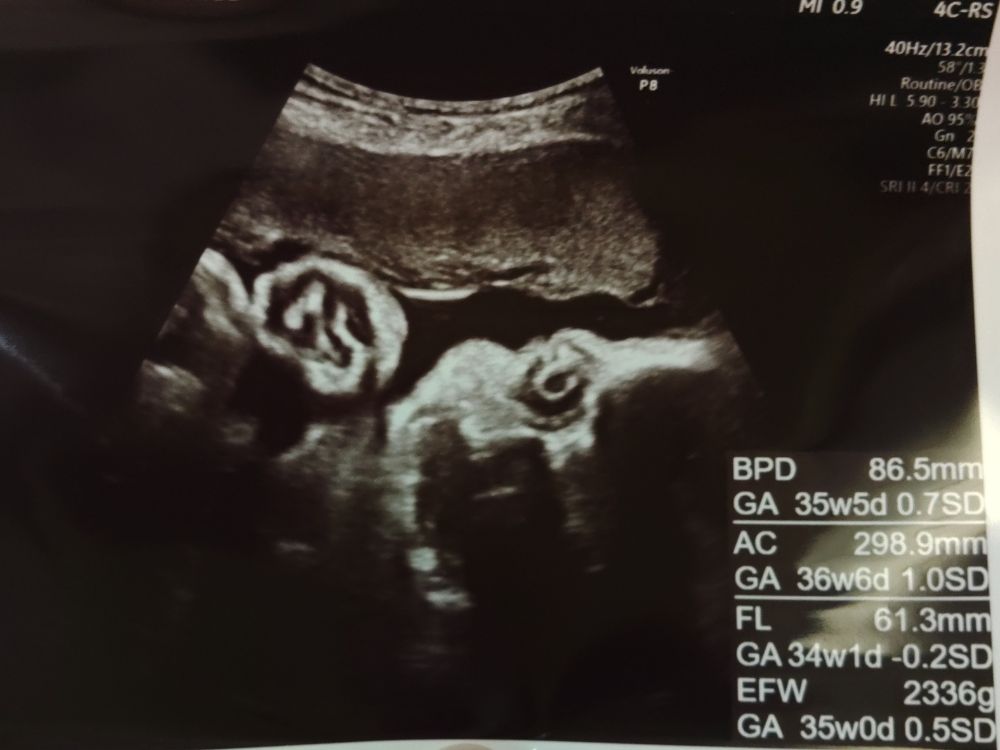

医師の診察|胎児体重は約2,336g

胎児モニターが終わったあとは、医師の診察へ。

超音波での確認の結果、

- 胎児体重は約2,336g

とのことでした。

3週間前(鹿児島での健診:1,807g)から、

+500gほど増えていて順調との評価。